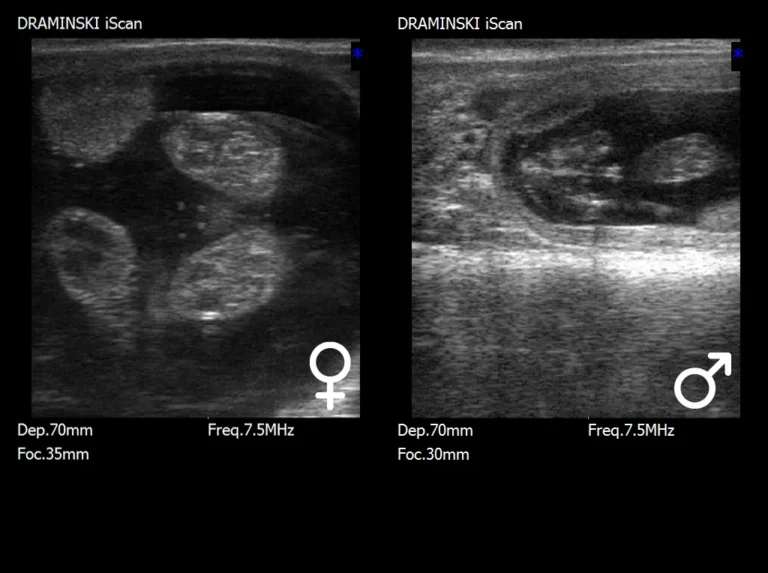

Urządzenia elektroniczne wspierające

hodowlę i rozród zwierząt gospodarskich

oraz psów.

Hodowla zwierząt

gospodarskich